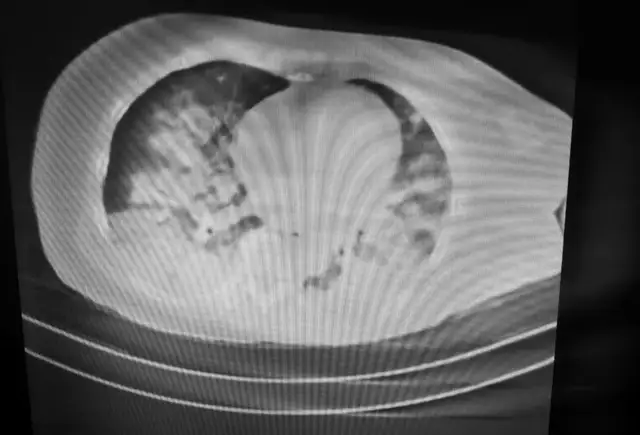

7月6日,62岁的陈某不慎落水,被救起后由当地医院救护车急送至湘潭县人民医院急诊科,入急诊科时患者神志昏迷,全身青紫、冰冷,呼吸极度窘迫,血氧饱和度30-40%,立即予以气管插管复苏囊辅助呼吸,查肺部CT提示双侧肺部大量渗出,"白肺"表现,病情十分危险,急转入重症医学科。

患者入ICU时重度缺氧,昏迷,重度酸中毒,休克,病情恶化迅速,气管内吸引出大量淡红色血性液体,呼吸机给100%氧浓度,氧合指数低于100,考虑重度ARDS,采用俯卧位通气,肺保护性通气策略(小潮气量,高PEEP),同时迅速成功进行深静脉穿刺,进行血流动力学评估和泵入血管活性药物维持血压,并给予纠酸、激素抗炎减少渗出,解除气管痉挛,加强抗感染等一系列治疗措施。